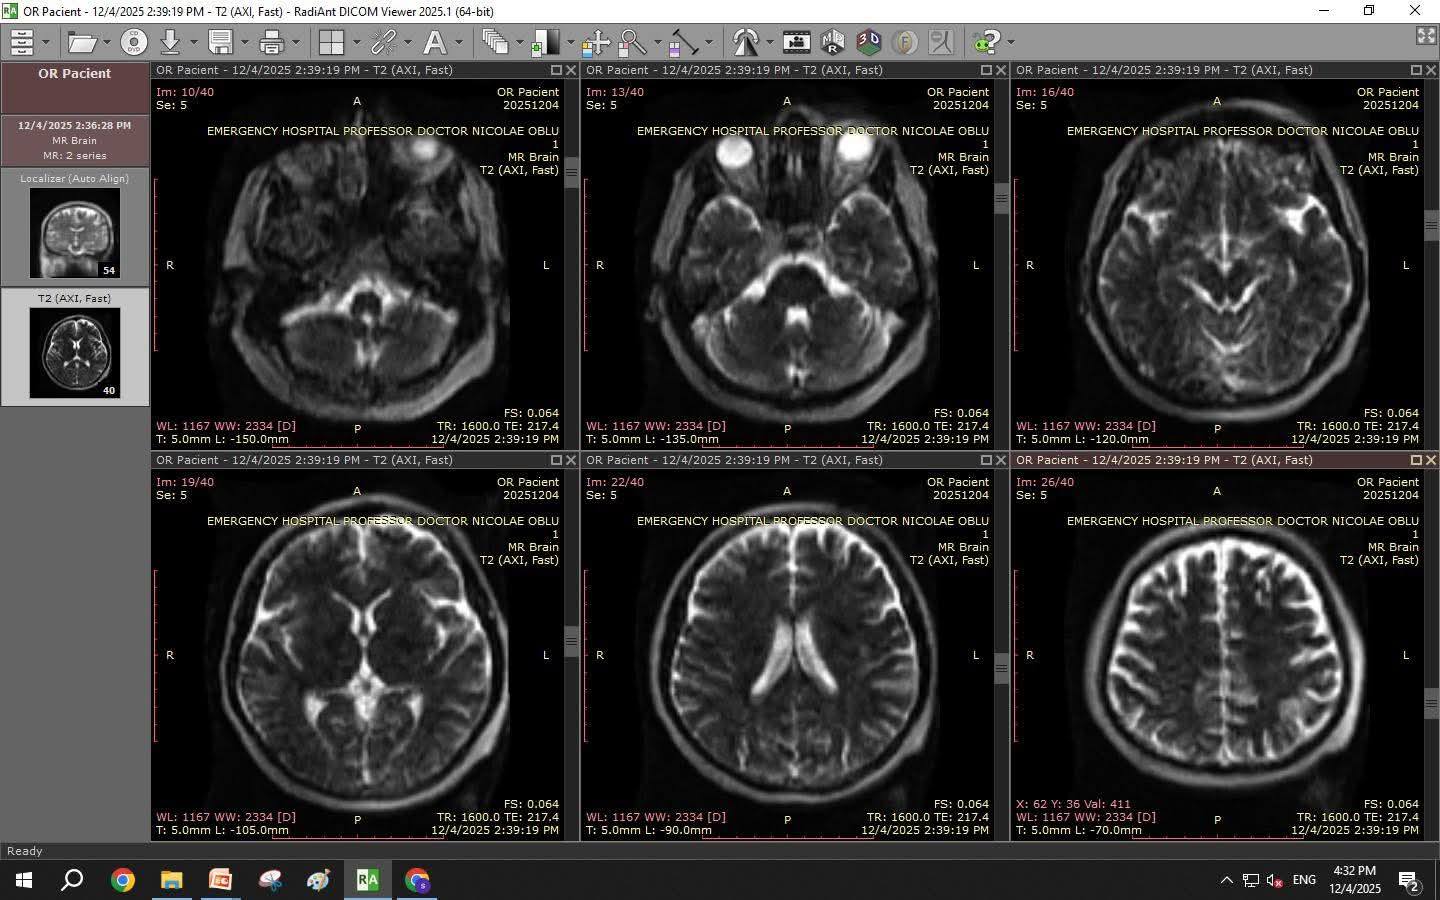

Se întâmplă la Spitalul „Prof. Dr. Nicolae Oblu” Iași, acolo unde se poate poate realiza investigații imagistice de înaltă performanță în timpul intervențiilor neurochirurgicale, direct în sala de operație și în terapie intensivă.

"Pentru prima dată în România introducem un sistem RMN mobil

Pentru prima dată, un spital din România poate realiza investigații imagistice de înaltă performanță în timpul intervențiilor neurochirurgicale, direct în sala de operație și în terapie intensivă.

Am vrut să văd cu ochii mei cum funcționează. Așa că mi-am făcut primul RMN în primul sistem RMN mobil din România: 6 minute.

Da, 6 minute, față de cele 60 de minute ale unui RMN clasic. Este incredibil unde putem ajunge când investim corect și cu viziune.